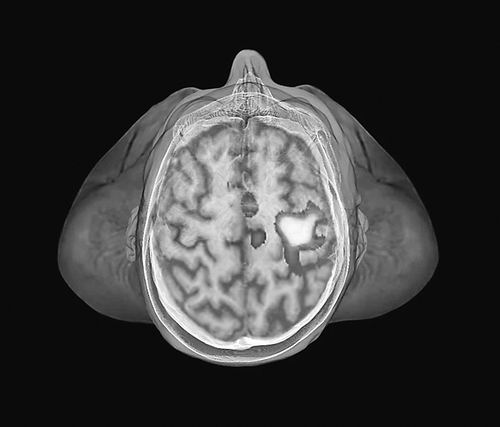

当受到感染威胁时,大脑活动可激活免疫细胞。图片来源:Zephyr/Science Photo Library

研究人员发现,传染性虚拟人像的靠近激活了与个人空间,即紧邻身体的区域相关的脑区。紧接着,大脑“突显网络”的活动激增,这是一个参与识别重要事件(如威胁)并对其作出反应的区域集合。